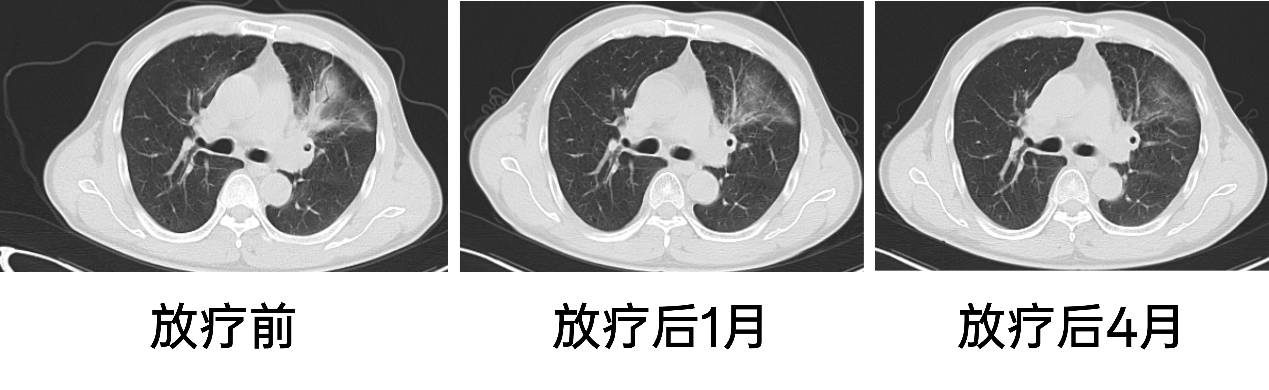

放疗:患者入院后完善相关检查检验,排除禁忌于2024年8月5日开始行放疗,靶区:右肺下叶病灶,剂量:50Gy/25Fx,于2024年9月6日完成放疗,放疗同期行白蛋白紫杉醇+卡铂治疗5周期,并予甘氨双唑钠增敏,期间出现化疗后骨髓抑制,经治疗后好转。治疗后患者咳嗽较前好转。

疗效评估:

放疗前:2024年7月29日,PET-CT:右肺癌治疗后:1、右下肺门处软组织肿块,FDG摄取增高,结合病史,考虑肺癌伴伴肺不张伴远端阻塞性炎症,病灶仍具有肿瘤活性。 2、左肺上叶尖后段微小结节,FDG未见异常摄取,建议CT定期随访。 3、双肺肺气肿;双肺散在慢性炎症。 4、肝脏囊肿。 5、所示椎体退行性变。

图3. 放疗前影像

放疗后1月:2024年10月胸部CT:右肺下叶膨胀不全,右肺下叶肺门旁团块影,结合病史考虑肿瘤治疗后改变;2. 右肺上叶后段、左肺下叶背段慢性炎症伴局部支扩。

图4. 放疗后1月

放疗后3月:2024年12月11日复查胸部CT:1. 右肺下叶肺门旁团块影,右肺下叶部分肺不张,较前(2024-10-16)病变范围大致相仿,结合病史考虑肿瘤治疗后改变;右肺炎症,较前新发,治疗后复查。2. 慢性支气管炎、肺气肿。左肺下叶条索影伴轻度支气管扩张。3. 附见:肝内小囊肿可能。